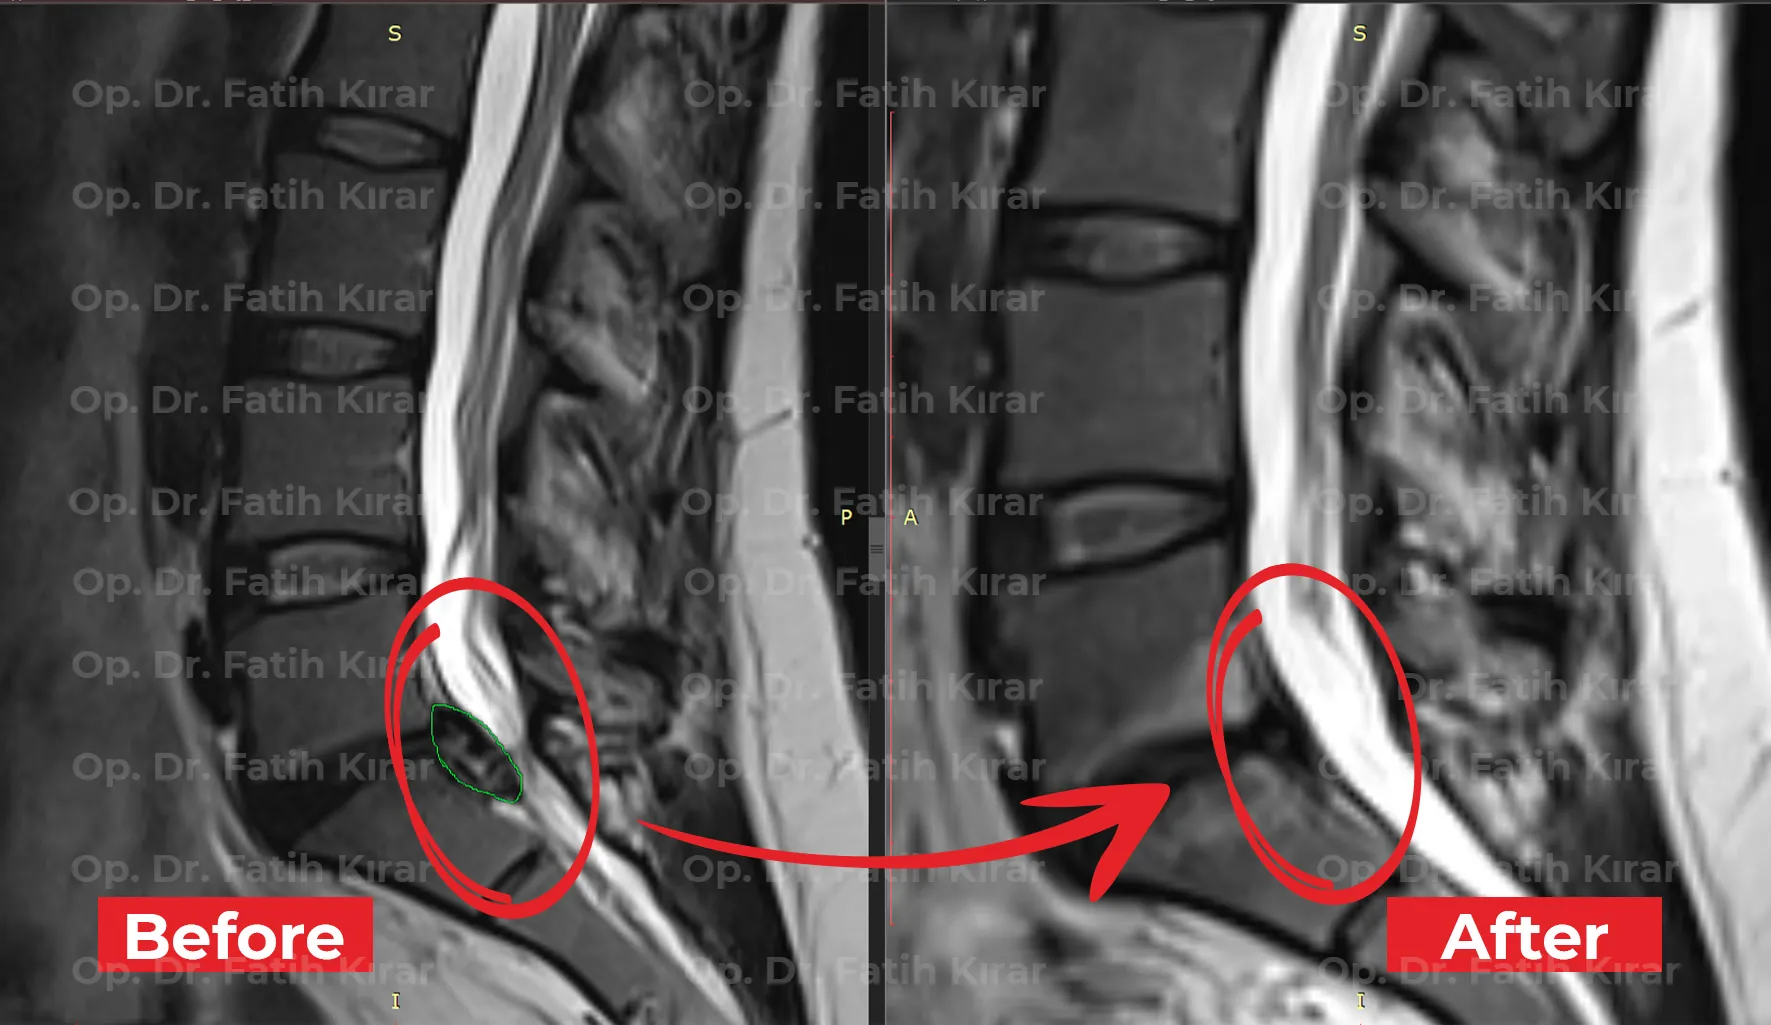

Gelişmiş fıtık tedavi sonuçlarımızdan gerçek önce ve sonra görüntüleri